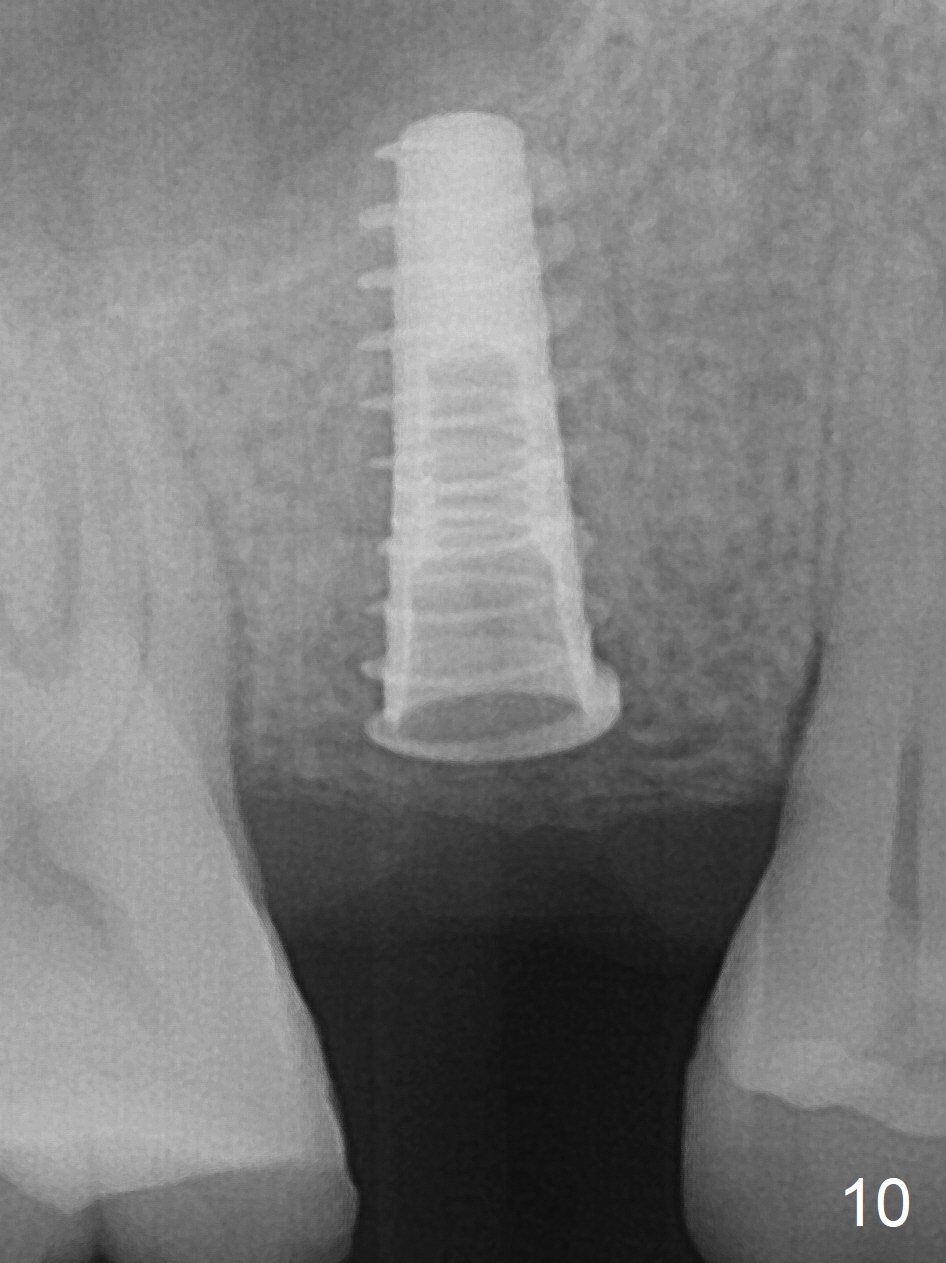

The implant dislodges while the abutment is untightened 8 months postop. The osteotomy is found intact. A 4.5x11 mm dummy implant is placed 2 mm subgingival with 20 Ncm (Fig.9). When a 4.5x11 mm definitive implant is placed 3 mm subgingival (Fig.10,11), torque reaches 50 Ncm. A 5.5x3 mm healing abutment is placed.